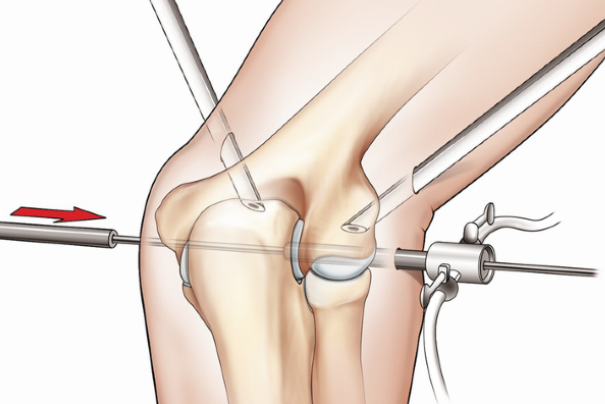

♦ 관절경 혹은 절개에 의한 점액낭 제거술

다음과 같은 경우에는 수술적 치료가 필요합니다.

☛2차 감염(고름, 열 동반)

☛ 재발이 심한 만성 점액낭염

☛보존적 치료 및 주사치료에 반응하지 않는 경우

☛최근에는 기존의 절개 방식보다 회복 속도가 빠른 관절경 수술이 일반적으로 선호됩니다.